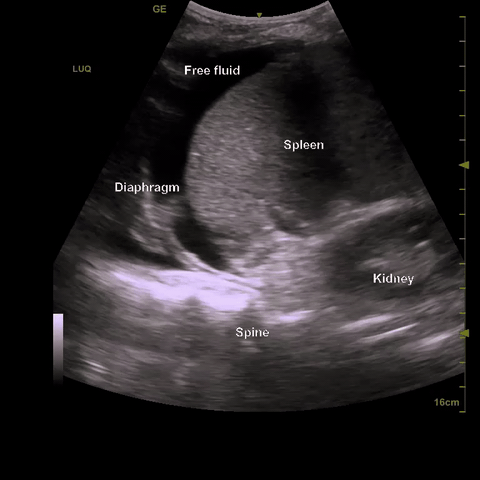

LUQ: Locate the xiphoid process and move laterally to the posterior axillary line on the left side with the probe in longitudinal orientation and scan until both the spleen and left kidney are in the same view and focus on the splenorenal interface. This is only a landmark however as the splenorenal interface does not really allow for fluid accumulation. Instead slide caudally to sub-diaphragmatic space and fan anterior to posterior through the whole space. Anechoic material in this space is positive for free fluid.

LUQ: Unlike the RUQ where fluid accumulates preferentially in the hepatorenal interface, there is little potential space in the splenorenal interface. Therefore the more sensitive location is in the sub-diaphragmatic space in the LUQ.